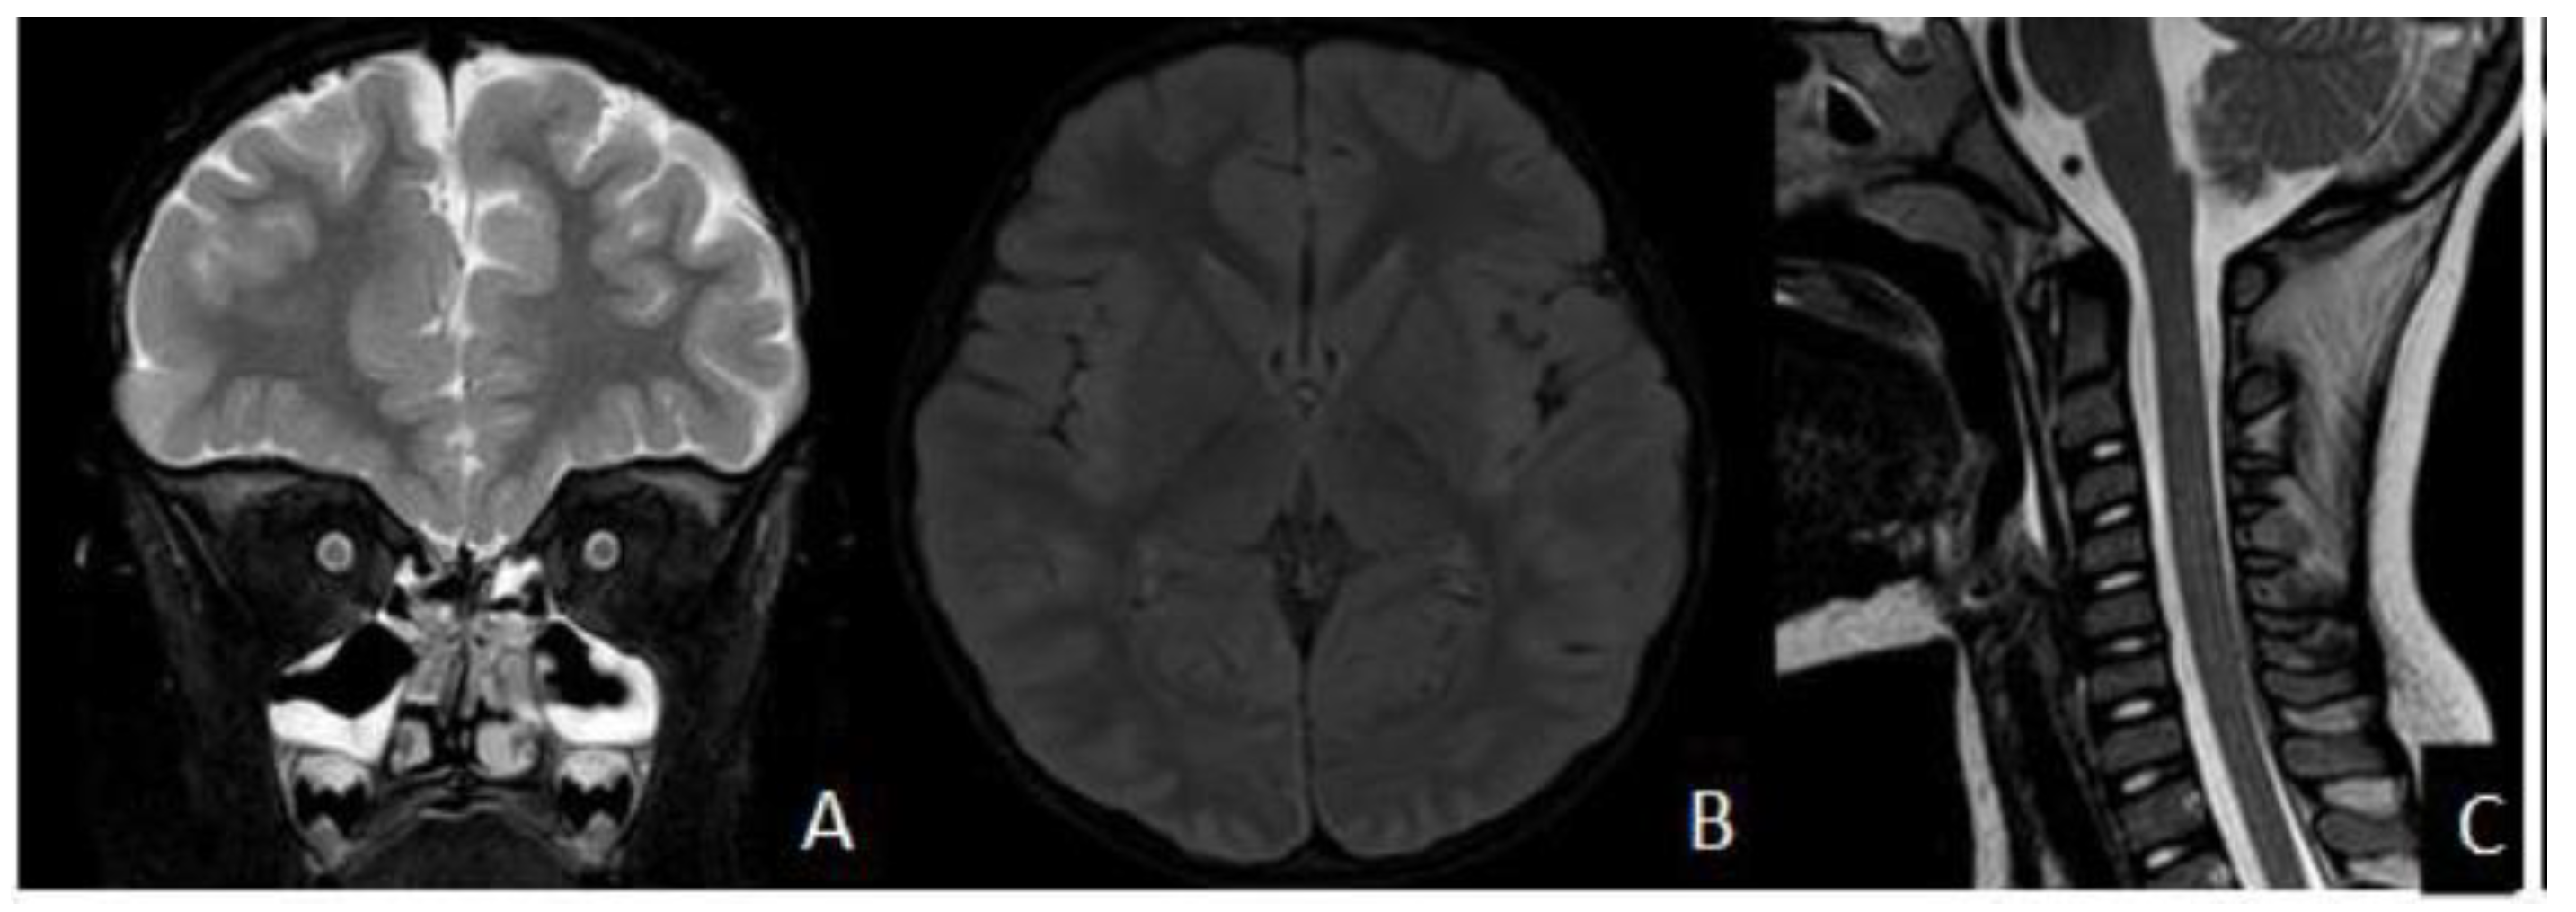

2. Case Presentation